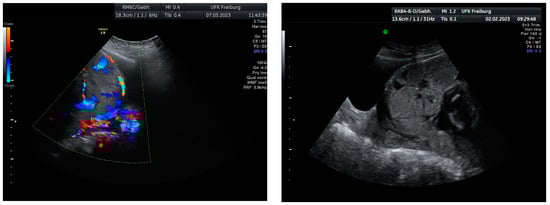

Sonographic findings (Figure 7):

Figure 7.

Revealed the following sonographic findings:

A very small barrier between the uterus and the bladder, with no recognizable

- myometrium in this area.

- Numerous blood vessels, most parallel and two perpendicular.

- Multiple placental lacunae confirmed by color Doppler.

Based on these findings, we planned an elective cesarean section at 35 weeks of gestation, combined with a hysterectomy due to the confirmed placenta increta and the high risk of significant bleeding. These findings were confirmed during the laparotomy.